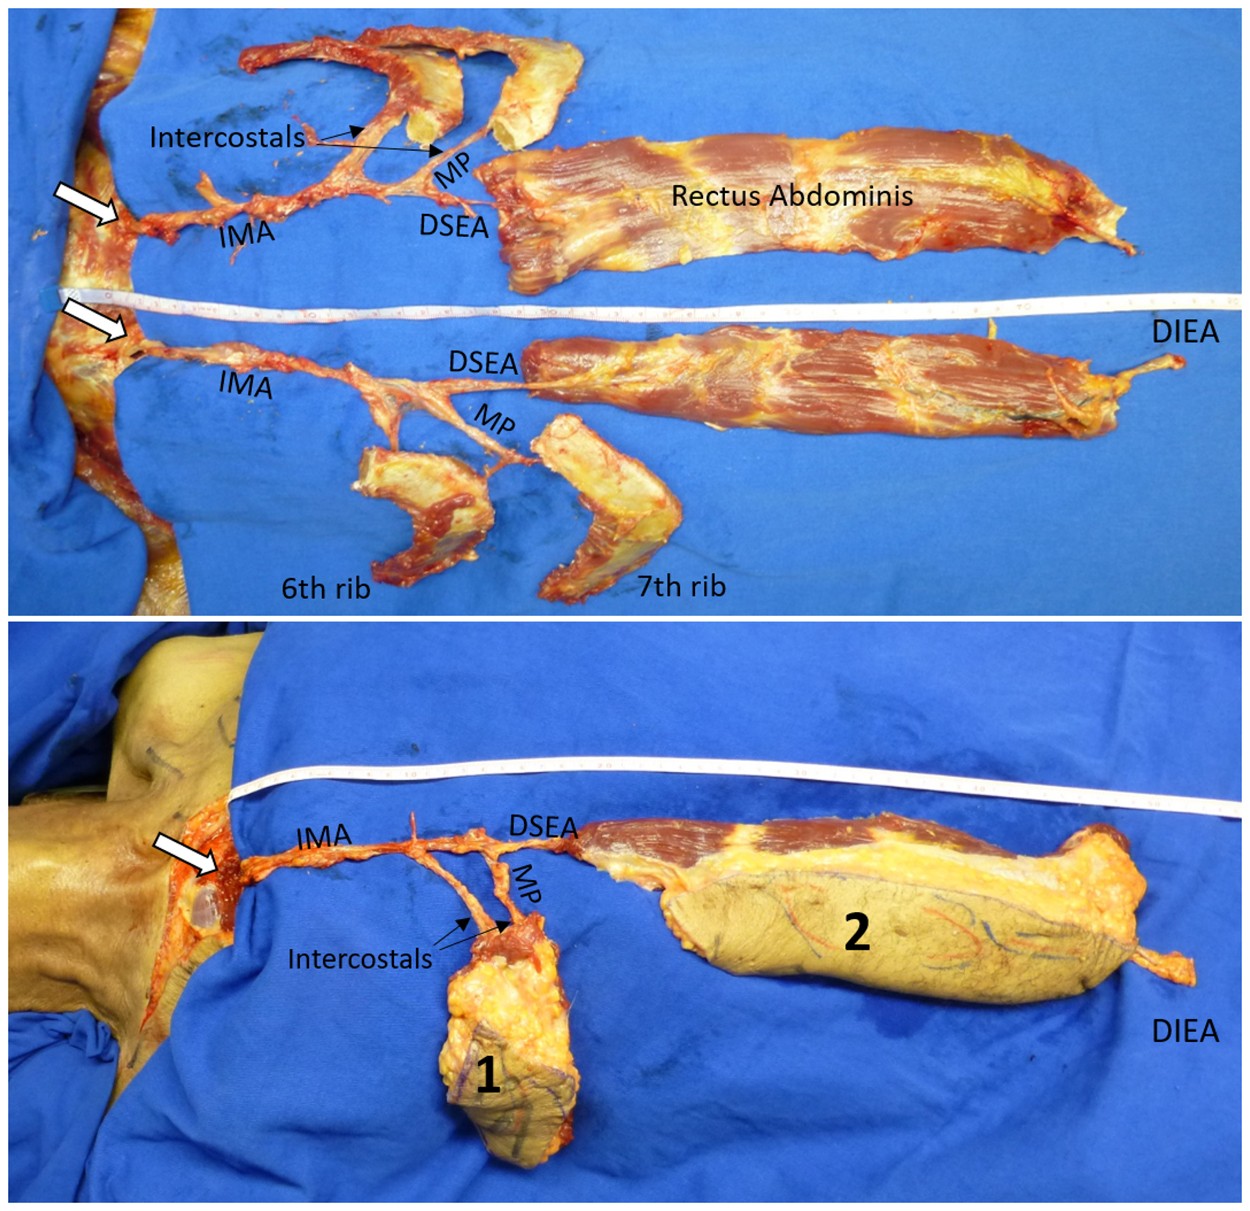

Figure 1

PIMOC cadaver dissection. (A) The IMA pedicle gives rise to the intercostal arteries and bifurcates distally into the musculophrenic (MP) artery and the deep superior epigastric artery (DSEA). The DSEA anastamoses with the DIEA after supplying the rectus abdominis. The 6th and 7th ribs are supplied by the MP and individual intercostal arteries. (B) The PIMOC with its IMA pedicle, osteomyocutaneous components including the 6th and 7th ribs (1), and myocutaneous vertical rectus abdominis component (2).